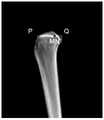

请参阅图8A,图8A是本发明提供的通过三维图像识别第四关键点与第五关键点确定的直线的投影并确定第二平行面的流程示意图,如图8A所示,在胫骨平台中前部第四预设距离处识别第四关键点和第五关键点,通过第四关键点和第五关键点做胫骨冠状面第二平行面至少包括:Please refer to FIG. 8A. FIG. 8A is a schematic flowchart of identifying the projection of the straight line determined by the fourth key point and the fifth key point through the three-dimensional image provided by the present invention and determining the second parallel plane. As shown in FIG. 8A, in the tibial plateau Identify the fourth key point and the fifth key point at the fourth preset distance in the front, and make the second parallel plane of the coronal plane of the tibia through the fourth key point and the fifth key point, including at least:

801,对包含胫骨与腓骨的三维图像做胫骨的矢状面投影,得到胫骨的矢状面图像。801. Perform a sagittal plane projection of the tibia on the three-dimensional image including the tibia and the fibula to obtain a sagittal plane image of the tibia.

802,在所得到的胫骨的矢状面图像中,识别胫骨近端最前侧点和最后侧点。802. In the obtained sagittal image of the tibia, identify the most anterior and posterior points of the proximal tibia.

803,在所识别的最前侧点与最后侧点之间沿图像横轴长度的第四预设距离处且靠近最前侧点处识别第四关键点,并识别通过第四关键点确定的直线在矢状面图像中的投影。803: Identify a fourth key point at a fourth preset distance along the length of the horizontal axis of the image between the identified foremost point and the rearmost point, and identify a fourth keypoint at a position close to the foremost point, and identify the straight line determined by the fourth keypoint at Projection in sagittal image.

804,通过所识别的直线在矢状面图像中的投影做一条平行于图像纵轴的直线,以所做的直线为第二平行面在矢状面图像中的投影,确定第二平行面。804. Create a straight line parallel to the longitudinal axis of the image through the projection of the identified straight line in the sagittal plane image, and determine the second parallel plane by using the straight line as the projection of the second parallel plane in the sagittal plane image.

在本发明实施例中,如图8B所示,可以对包含胫骨与腓骨的三维图像做胫骨的矢状面投影,得到胫骨的矢状面图像,可以以矢状面图像右上角为坐标原点,以图像横轴方向为Y轴的正方向,以图像纵轴方向为Z轴的正方向,建立二维直角坐标系。然后计算矢状面图像上胫骨部分所有像素点的y坐标,并按照从小到大的顺序进行排列,将其中y坐标最小的点识别为胫骨最前侧点P,将其中y坐标最大的点识别为胫骨最后侧点Q。在识别出胫骨最前侧点P和胫骨最后侧点Q之后,计算沿图像横轴胫骨最前侧点P与胫骨最后侧点Q之间的距离h,将位于Q点左侧第四预设距离*h处胫骨上的点识别为第四关键点M和N的连线MN在矢状面图像中的投影,例如第四预设距离为1/3。通过连线MN在矢状面图像中的投影做一条平行于图像纵轴的直线,以这条直线作为第二平行面F在矢状面图像中的投影,来确定第二平行面F。In the embodiment of the present invention, as shown in FIG. 8B , the sagittal plane projection of the tibia can be performed on the three-dimensional image including the tibia and the fibula to obtain the sagittal plane image of the tibia, and the upper right corner of the sagittal plane image can be used as the coordinate origin, Taking the horizontal axis of the image as the positive direction of the Y-axis, and taking the vertical axis of the image as the positive direction of the Z-axis, a two-dimensional Cartesian coordinate system is established. Then calculate the y-coordinates of all the pixels of the tibia on the sagittal plane image, and arrange them in ascending order. The point with the smallest y-coordinate is identified as the most anterior point P of the tibia, and the point with the largest y-coordinate is identified as Q at the rearmost lateral point of the tibia. After identifying the most anterior point P of the tibia and the posterior point Q of the tibia, calculate the distance h between the most anterior point P of the tibia and the posterior point Q of the tibia along the horizontal axis of the image, which will be located at the fourth preset distance to the left of the Q point* The point on the tibia at h is identified as the projection of the connecting line MN of the fourth key points M and N in the sagittal plane image, for example, the fourth preset distance is 1/3. The second parallel plane F is determined by drawing a straight line parallel to the longitudinal axis of the image by connecting the projection of the line MN in the sagittal plane image, and using this straight line as the projection of the second parallel plane F in the sagittal plane image.